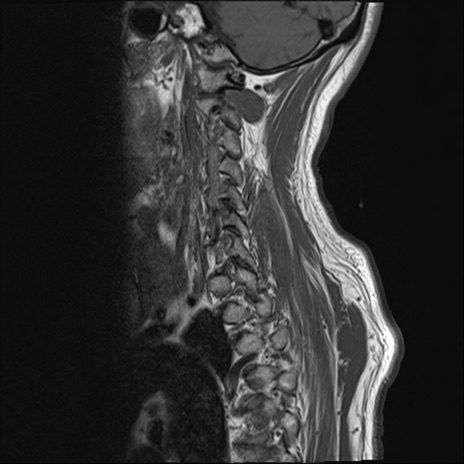

【整形】TIPS症例7 頚椎MRI T1WI(矢状断像)

頚椎MRI

T2WI(矢状断像)

矢状断像と横断像